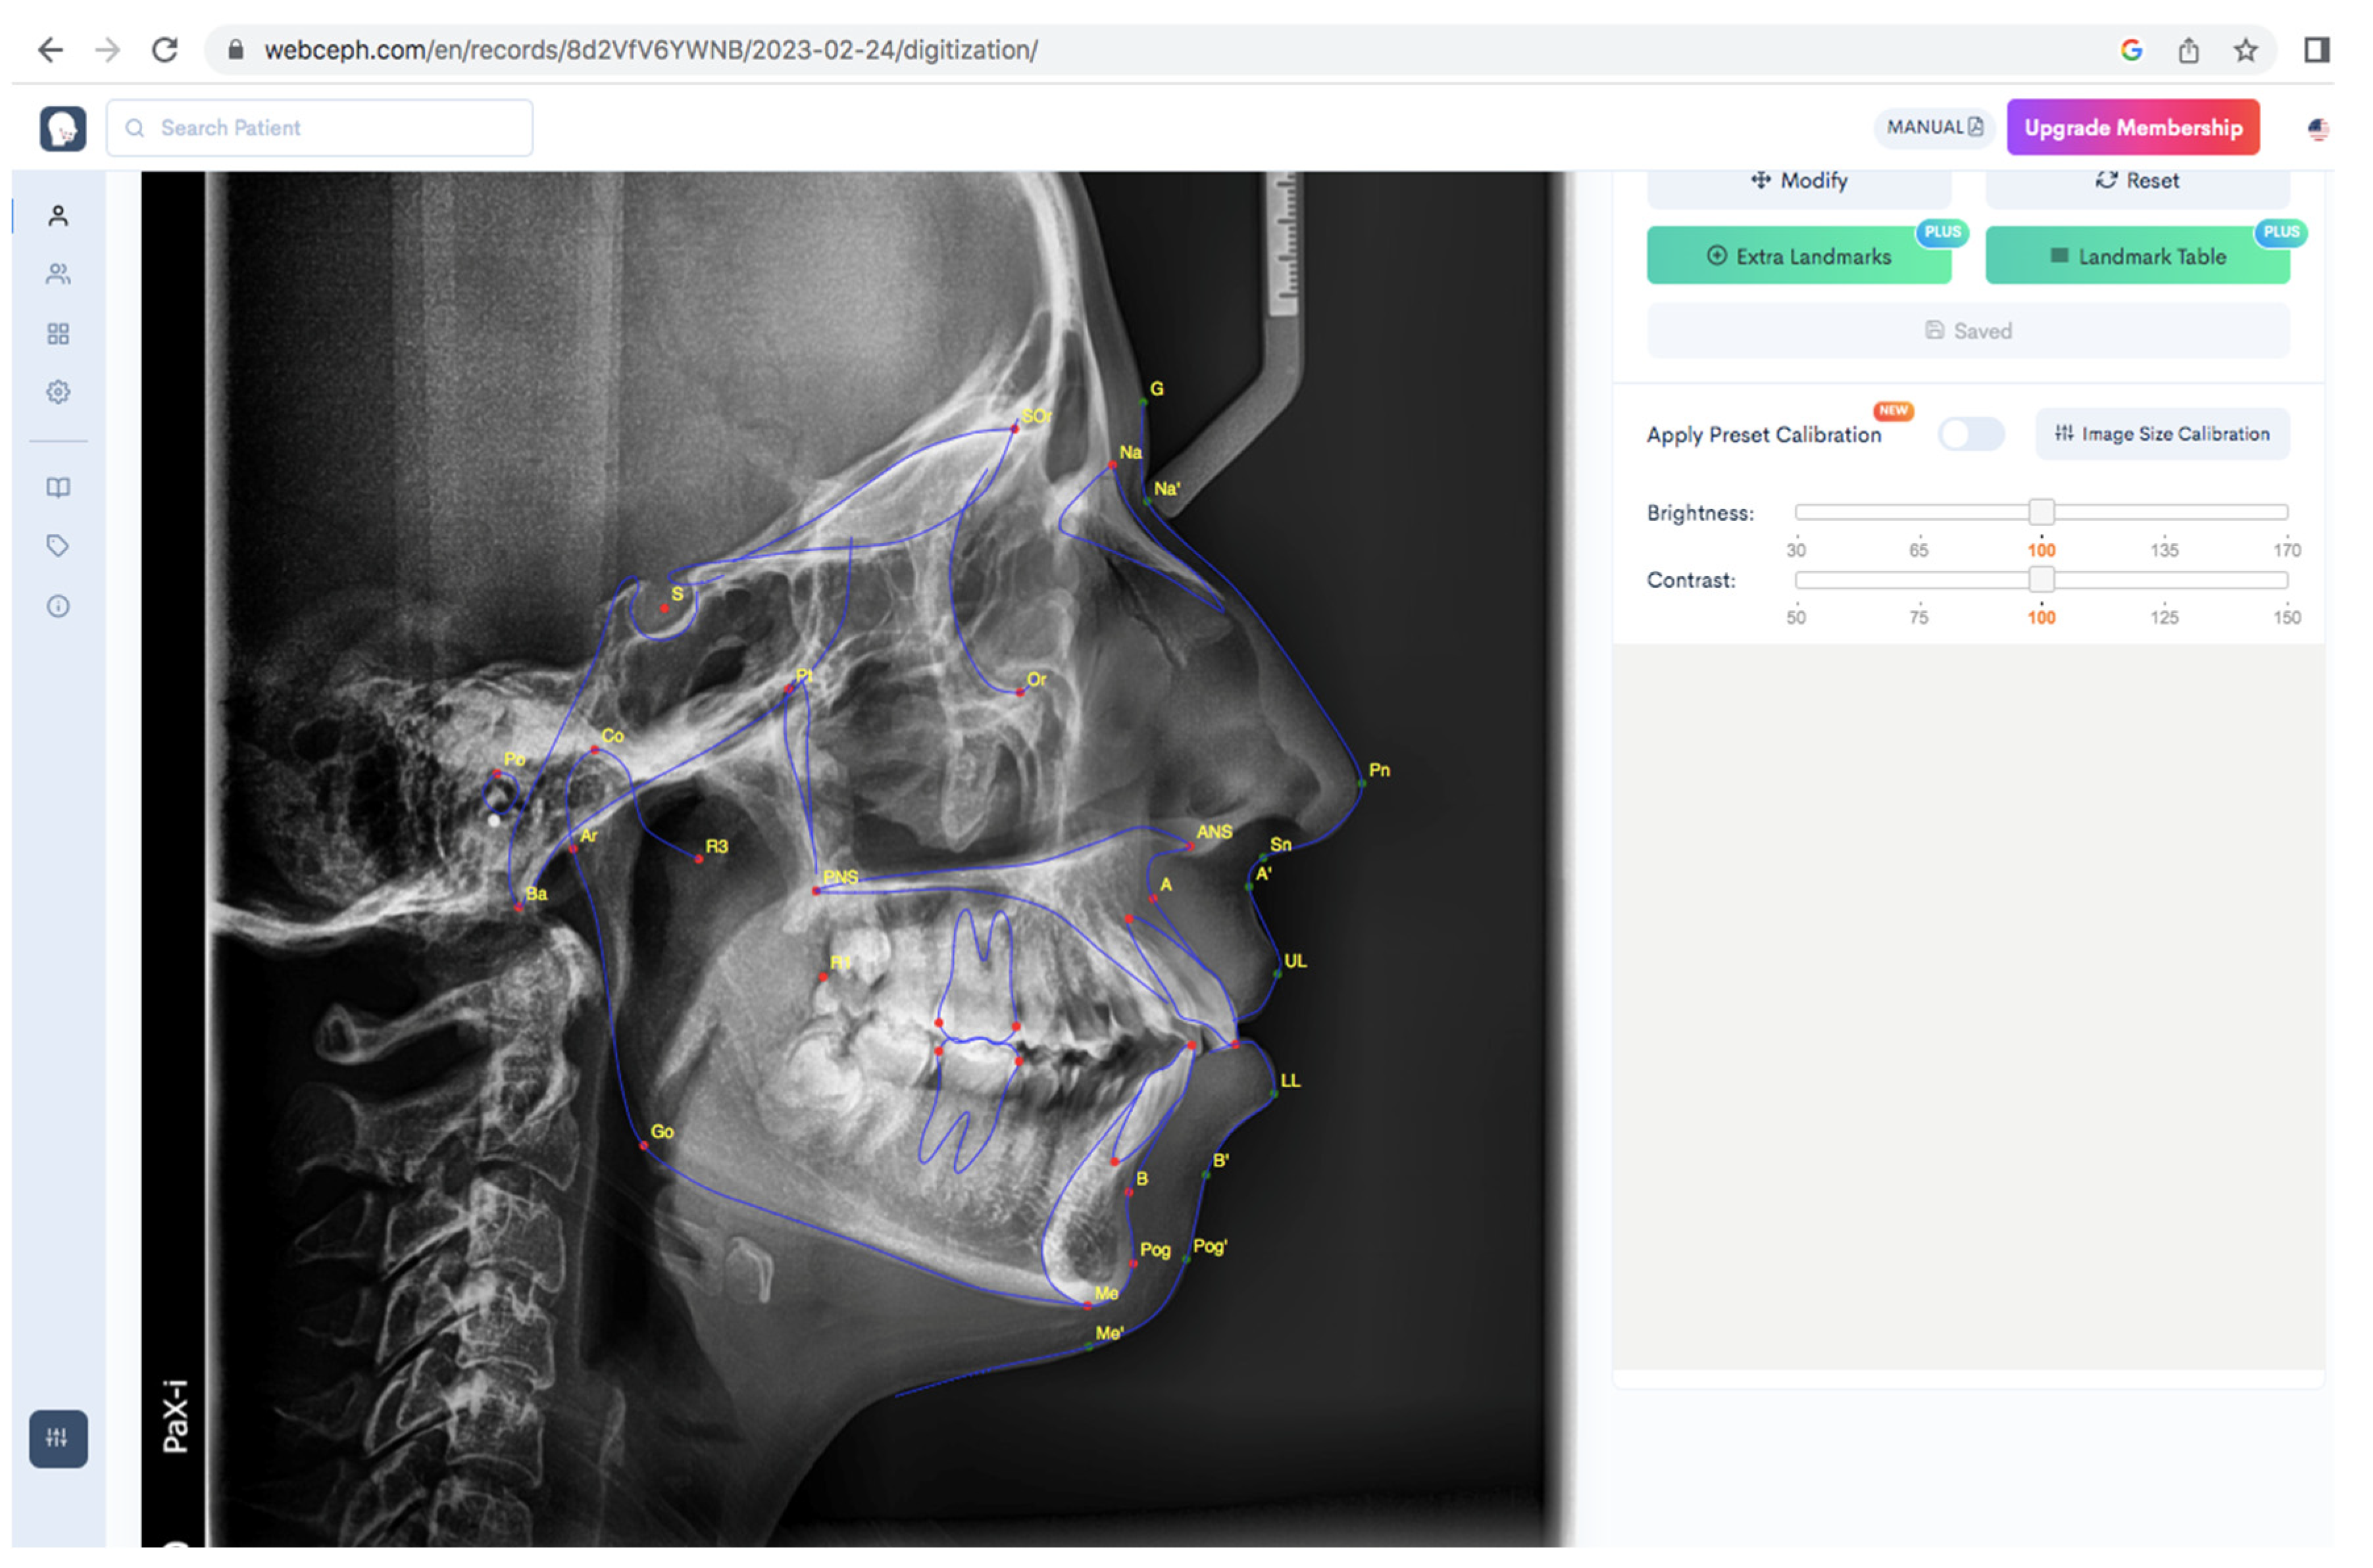

2.4. Cephalometric Analysis